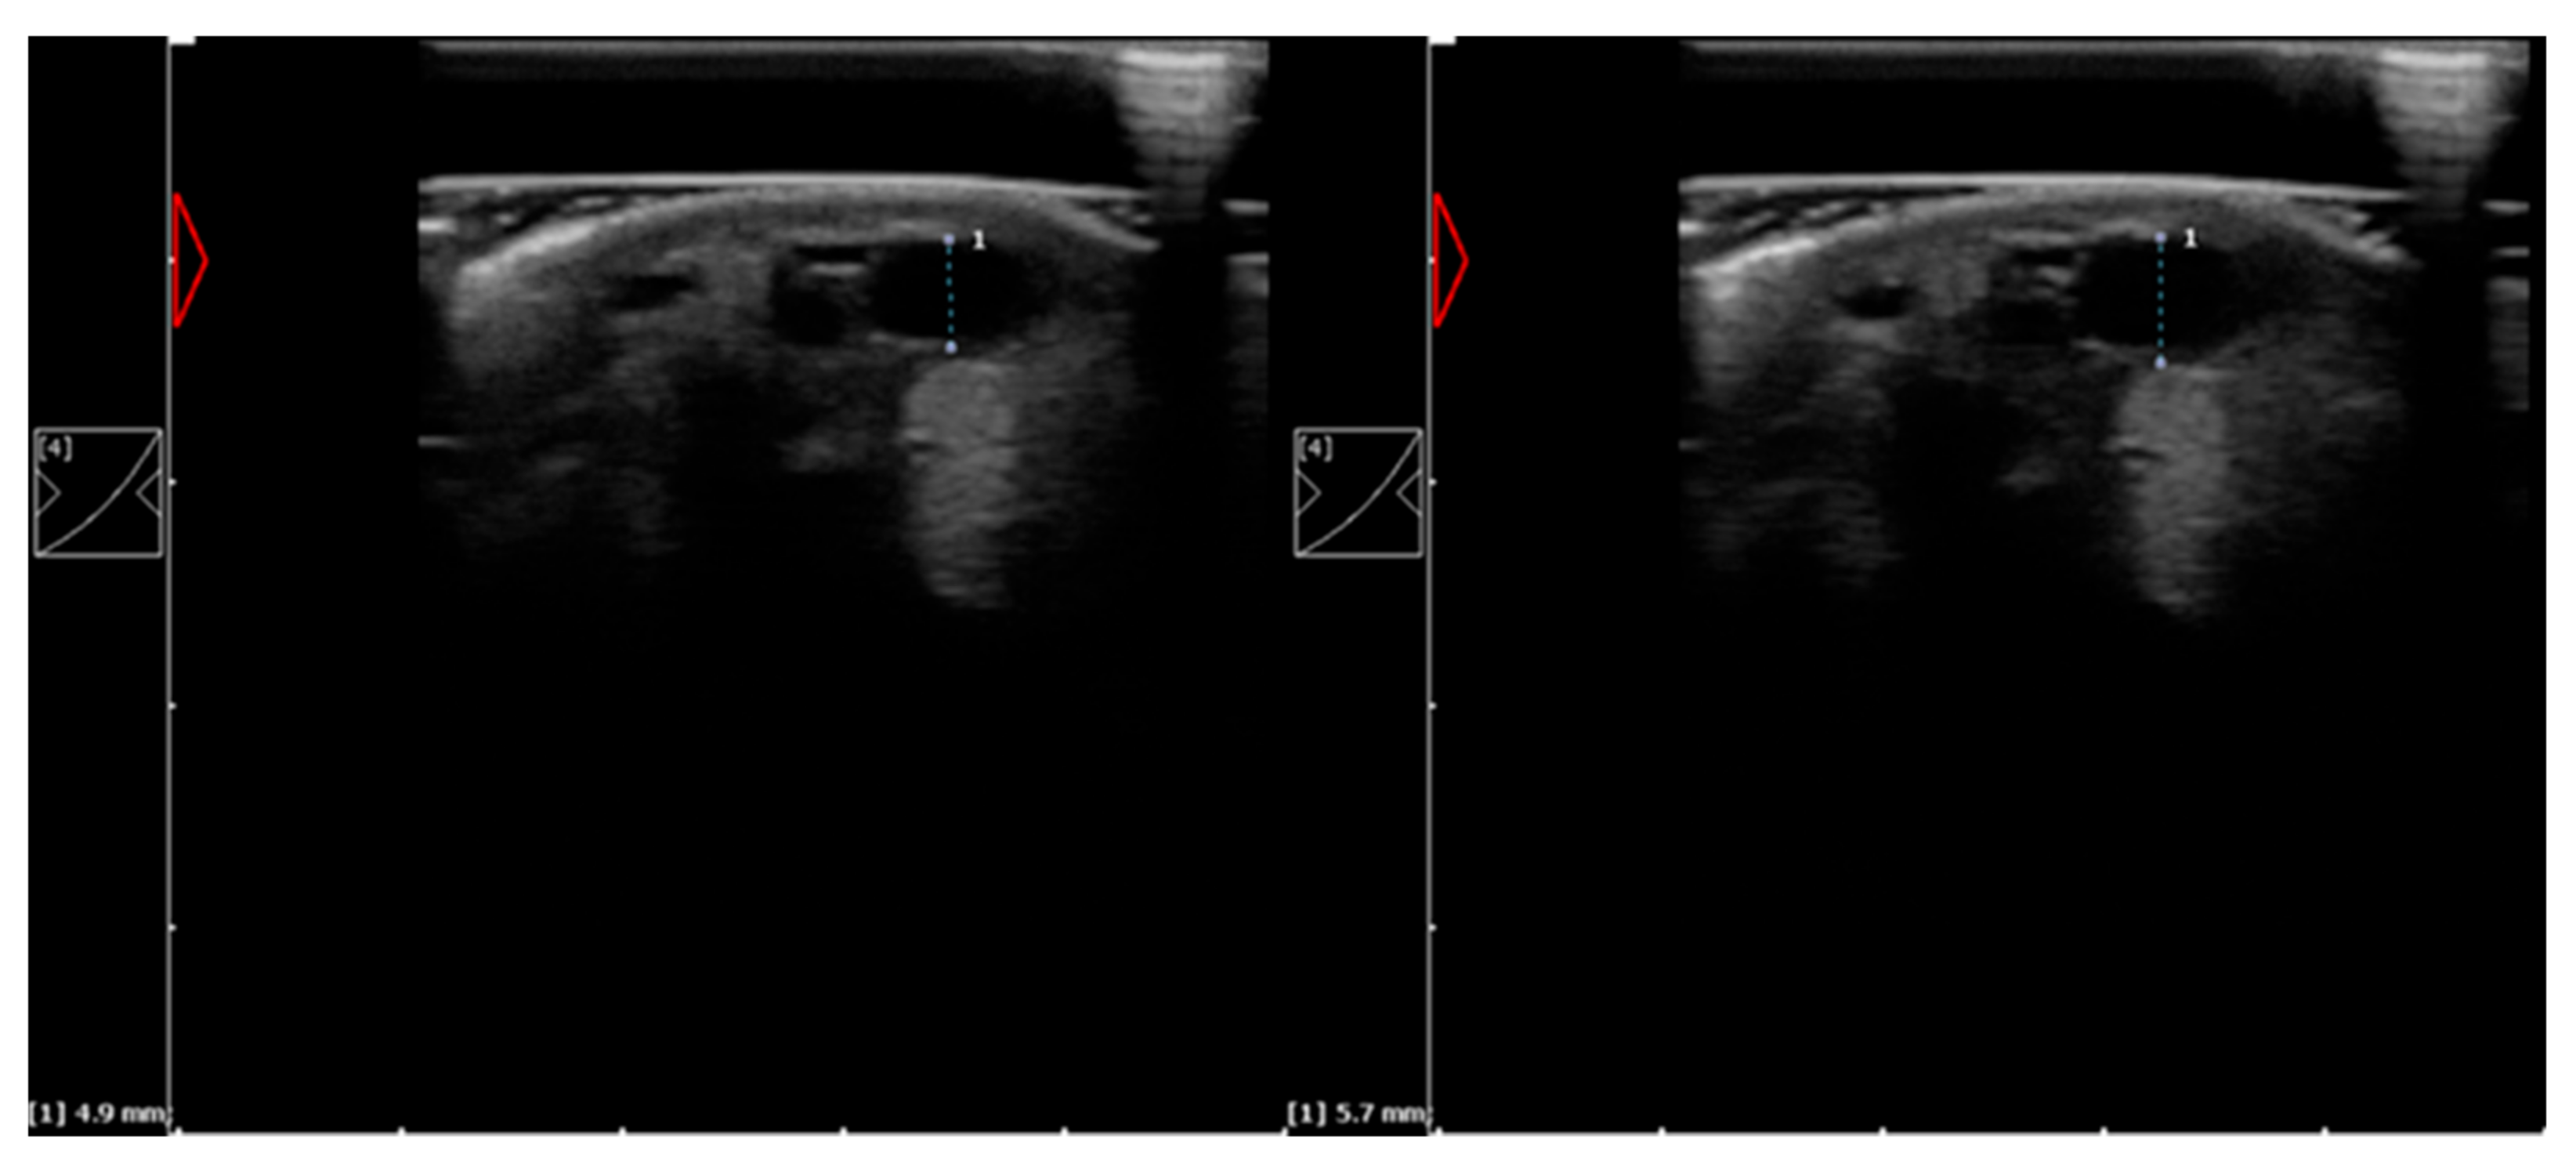

2.3. Ultrasound Examination

Skin Surface Temperature and Vein Diameter